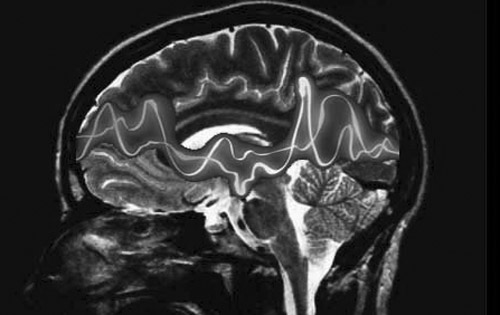

Por su parte la Sociedad Española de Neurología (SEN) ha puesto hincapié en los avances producidos en el conociento de la fisiopatología de la epilepsia, en los métodos diagnósticos y en los tratamientos existentes que permiten que el 70% de los pacientes epilépticos puedan vivir con normalidad. Y ha apostado la cirugía, la estulación cerebral o la aparición de nuevos fármacos como las pautas que marcarán el futuro de la epilepsia.